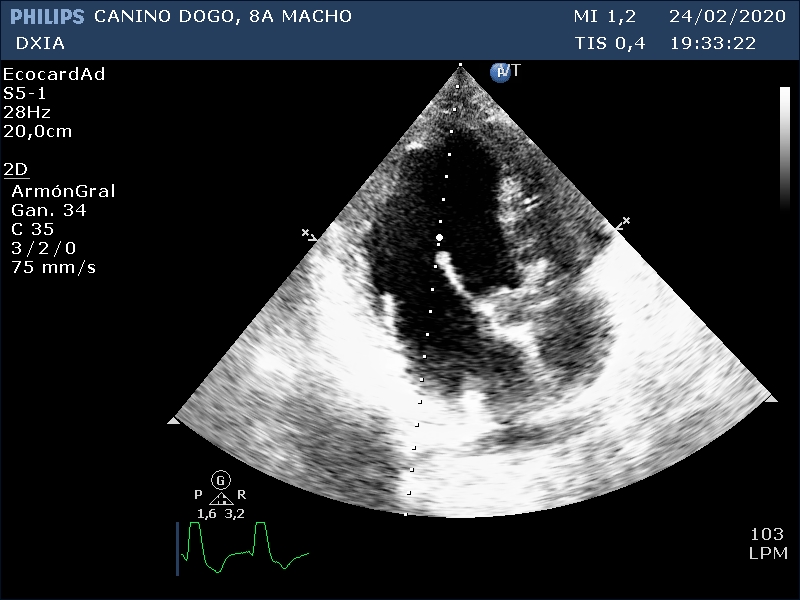

Corte apical izquierdo 4 cámaras. Observamos aumento de cámaras cardiacas, cambios grosores paredes

Comentario respecto al estudio ecocardiográfico:

- Agrandamiento de cámaras derechas e izquierda con disminución grosores paredes cardíacas.

- Valva septal de la VM levemente engrosada con patrón nodular ¿degeneración?

- Varios indicadores de cambios compatibles con fenotipo de CMD.

- ECG fibrilación atrial.